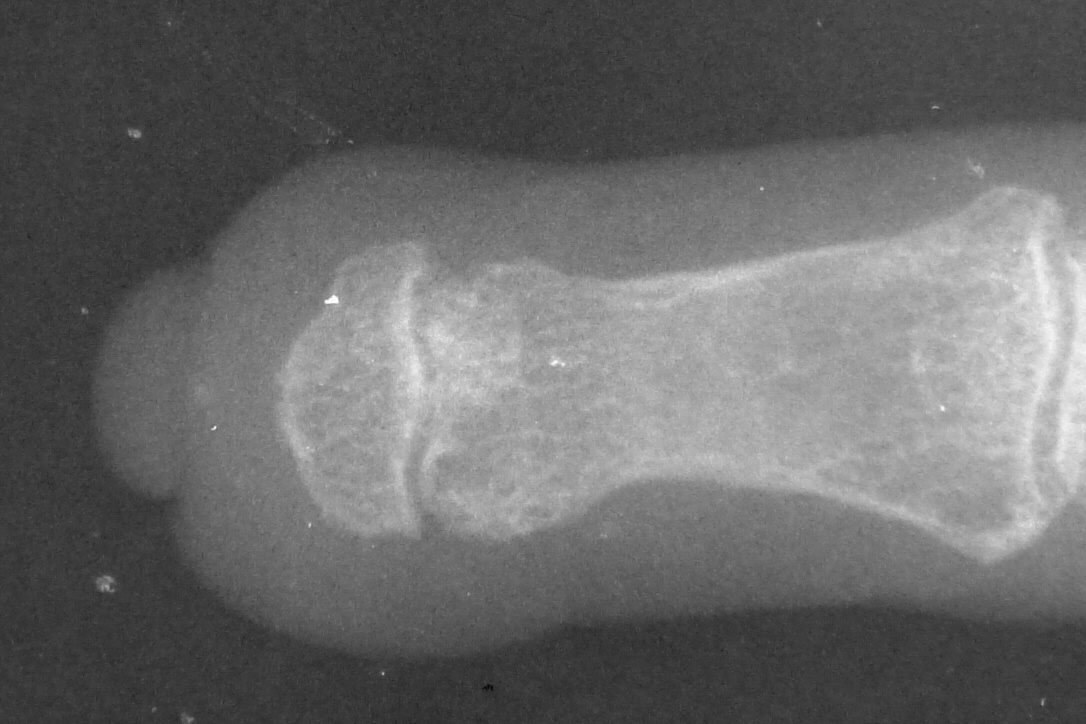

The tip graft progressively resorbed, and by six years after reconstruction, the hook nail deformity has recurred completely.

Xrays over this period: initial deformity, bone graft, and progressive bone graft loss over the course of years:

Image Image